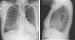

Abbildung 1: Thoraxröntgen

Thoraxröntgen p.a.